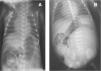

El recién nacido presentaba en el momento de su ingreso un abdomen globuloso con diástasis de rectos y hernia umbilical (fig. 1A), criptorquidia bilateral y atresia anal (fig. 1B), así como un pulgar de implantación proximal, sin ningún rasgo fenotípico facial característico.